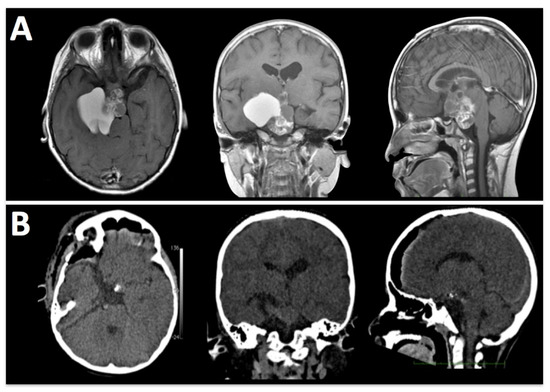

Figure 5. A 10-year-old girl with a history of headaches, visual disturbances, and panhypopituitarism. (A) Pre-operative MRI shows a mixed lesion with cystic and solid components. (B) A post-operative CT scan demonstrates the removal of tumoral tissue from sellar, parasellar, and suprasellar compartments. The histopathological analysis confirms the clinical suspicion of craniopharyngioma.

The E-SRA technique allows for access to various structures in the skull base. The subfrontal corridor provides access to the olfactory nerves, optic nerves, inter-optic space, chiasm, lamina terminalis, A1 segment of the anterior cerebral artery, and anterior communicating artery. Dissecting Liliquist’s membrane allows for access to the interpeduncular cistern, posterior cerebral arteries, superior cerebellar arteries, basilar tip, and trunk. Figure 5 and Figure 6 and Video S2.